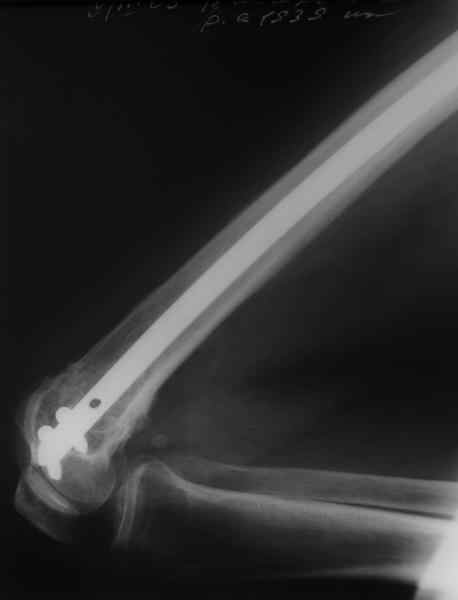

Чтобы больной не смог сгибать колено, выстоять в сустав железо должно

побольше значительно, чем на 1 мм. В приложении снимок с выстоянием

ммм на 3, видна и функция колена. Хотя клиника импинджмента была, но

даже не на один восклицательный знак. После удаления стержня проблемы

и вовсе рассосались.